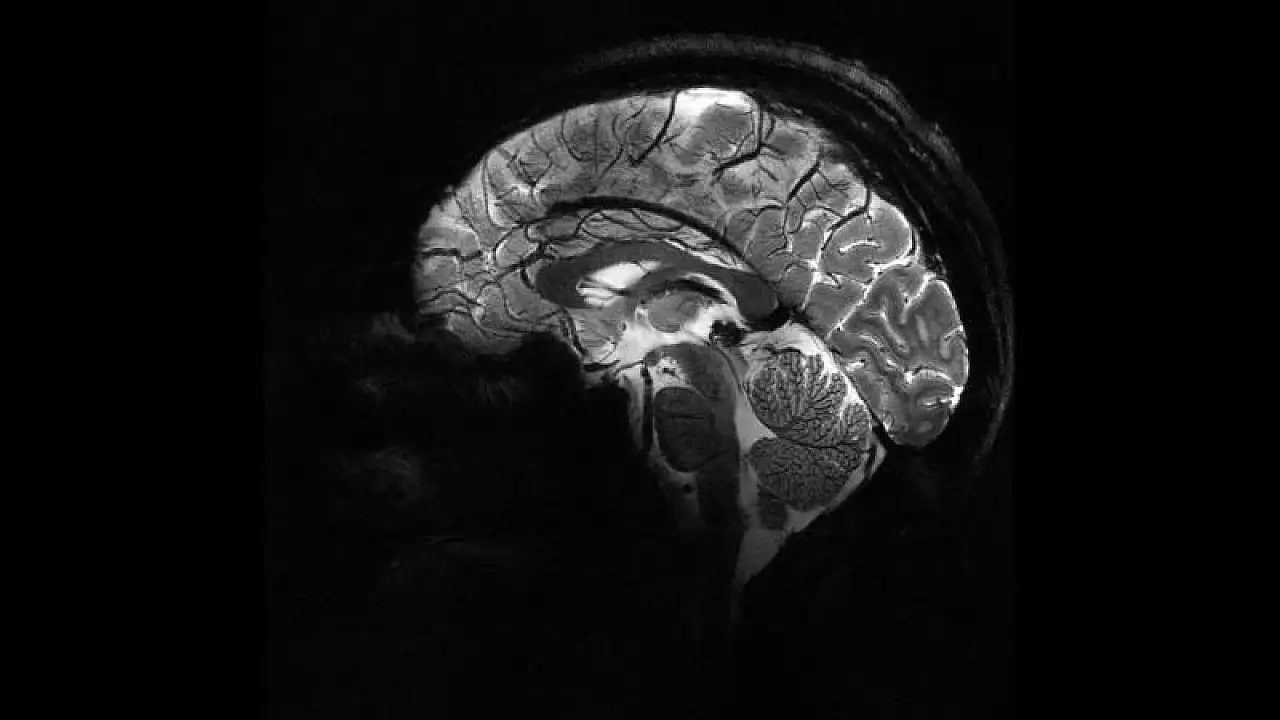

Pandemi beyinleri hızla yaşlandırdı

İngiltere'de yapılan bir araştırmaya göre, COVID-19 döneminde insanların beyinleri 2020 öncesine kıyasla ortalama 5,5 ay daha hızlı yaşlandı.Üstelik bu artış, COVID geçirmeyenlerde de görüldü.

İngiltere’de yapılan bir araştırmaya göre, COVID-19 döneminde insanların beyinleri 2020 öncesine kıyasla ortalama 5,5 ay daha hızlı yaşlandı. Üstelik bu artış, COVID geçirmeyenlerde de görüldü. Uzmanlar değişimlerin tersine dönebileceğini söylüyor.

Nottingham Üniversitesi’nden bilim insanları, UK Biobank’ta yer alan 15 binden fazla yetişkinin verileriyle sağlıklı beyin yaşlanmasını tanıyan bir yapay zekâ modeli geliştirdi. Model, pandemiden önce tarananlarla, önce ve pandemi sırasında taranan iki grubun beyin yaşlarını karşılaştırdı.

Araştırmaya göre, pandemi sürecinde insan beyninin yaşlanma hızı ortalama 5,5 ay öne çekildi.

Çalışmayı yürüten nörolog Ali-Reza Mohammadi-Nejad, “COVID geçirmeyenlerde bile belirgin artış gördük. İzolasyon ve belirsizlik gibi faktörler beyin sağlığını etkiledi” dedi.

Çalışmada beyin yaşındaki artışın, bilişsel performansı mutlaka düşürmediği vurgulandı; bilişsel gerileme yalnızca virüsle enfekte olanlarda saptandı.

Erkeklerde, gri ve beyaz maddede değişimlerin daha belirgin olduğu raporlandı.

Yaşlılar ile sosyal/ekonomik açıdan dezavantajlı gruplarda hızlanmış yaşlanma işaretleri öne çıktı.